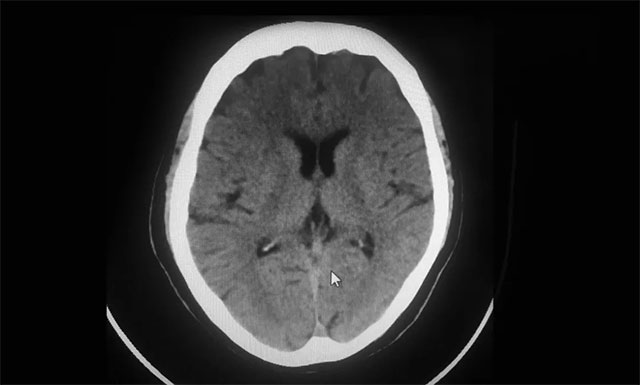

▲ 影像科平掃CT:排除腦出血

從急診科14:37接診,患者14:43建立靜脈通道,到14:56影像科平掃CT排除腦出血,并告知家屬征得同意,再到15:17接受溶栓,急診科、腦血管病科、影像科、檢驗(yàn)科等多個(gè)科室通力合作,發(fā)揮多學(xué)科聯(lián)動(dòng)優(yōu)勢(shì),無縫對(duì)接,DNT用時(shí)為40分鐘,為搶救患者的大腦功能贏得了寶貴時(shí)間。